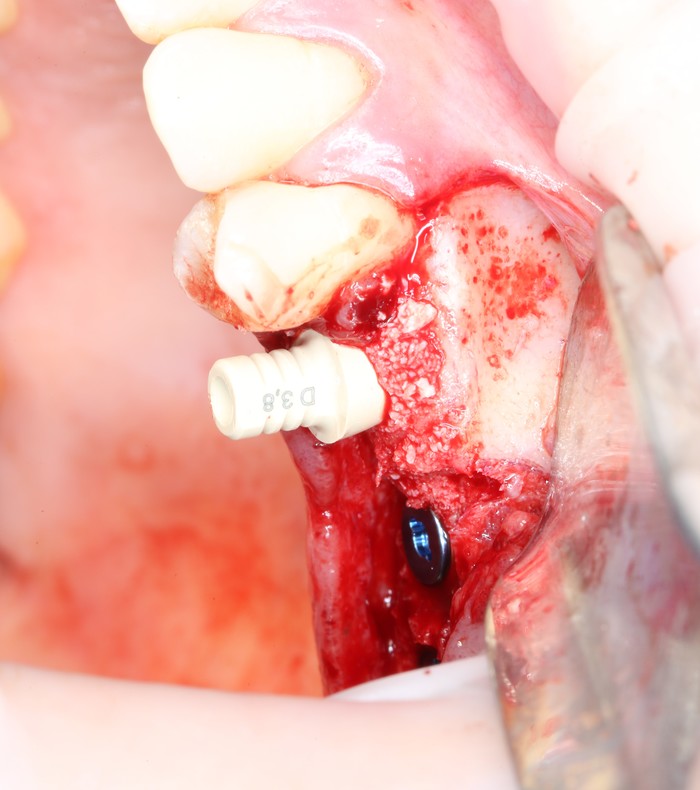

Дабы не перегружать вас обилием одинаковых картинок, я оставлю один рентгеновский снимок, но отмечу, что установка имплантатов на верхней и нижней челюсти проводилась с разницей в 10 дней.

На верхней челюсти было дополнительно удалено два боковых резца с одномоментной установкой имплантатов, так же они были установлены в области четверок и шестых зубов. Дополнительно было проведено наращивание костной ткани - двусторонний синус - лифтинг. О том, что это такое, можно почитать ТУТ и ТУТ.